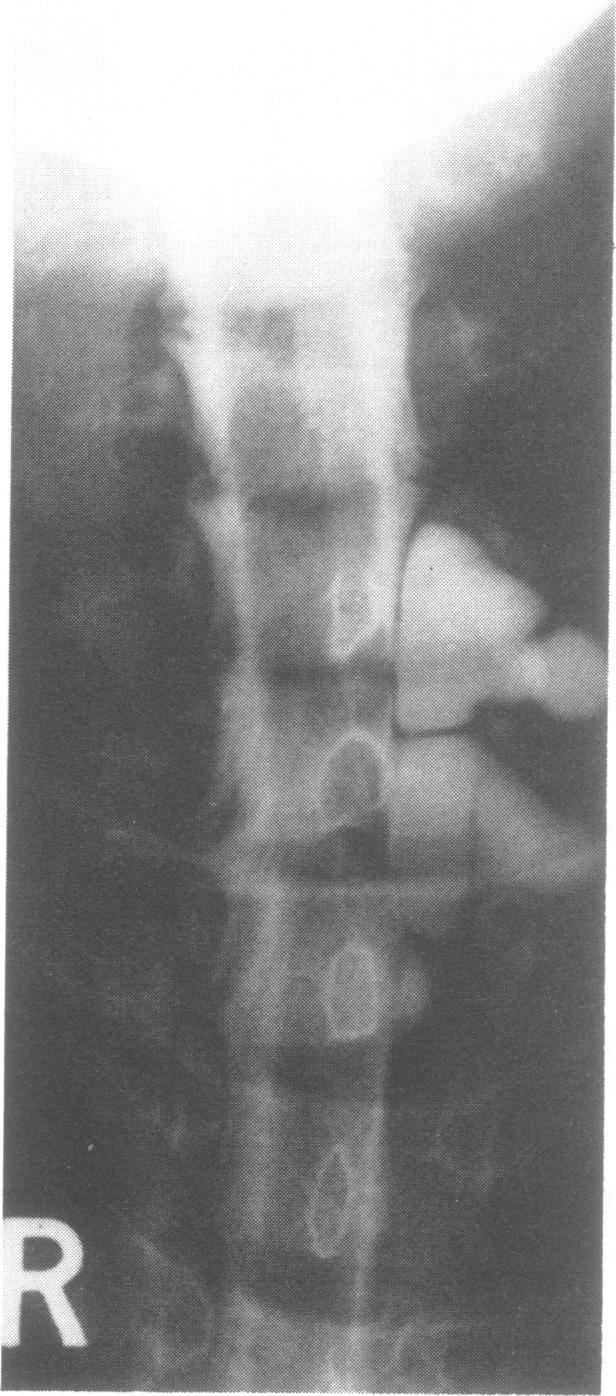

Dorsal root entry zone lesions (Nashold's procedure) for pain relief following brachial plexus avulsion.

Brachial plexus avulsion is an important cause of severe intractable pain, particularly in young motor cyclists. The pain usually develops soon after the injury. In a minority of cases severe pain persists and is refractory to management. Nineteen patients are reviewed in whom dorsal root entry zone lesions have been produced for pain relief. The operative technique is described. Early post-operative motor or sensory disturbance in the ipsilateral leg have been temporary side effects, with mild persisting deficits in a minority. Sixteen cases have had significant persisting pain relief. The maximum follow-up period is 2 1/2 years.